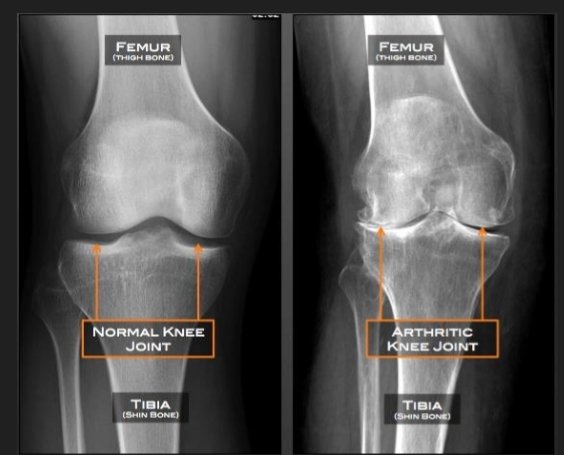

The diagnosis of knee osteoarthritis will begin with a phusical exam by your doctor. Your doctor will also take your medical history and note any symptoms. Make sure to note what makes the pain worse or better to help your doctor determine if osteoarthritis, or something else, may be causing your pain. Also find out if anyone else in your family has arthritis. Your doctor may order additional testing, including:

- X-rays, which can show bone and cartilage damage as well as the presence of bone spurs

MRI scans may be ordered when X-rays do not give a clear reason for joint pain or when the X-rays suggest that other types of joint tissue could be damaged. Doctors may use blood tests to rule out other conditions that could be causing the pain, such as rheumatoid arthritis, a different type of arthritis caused by a disorder in the immune system.